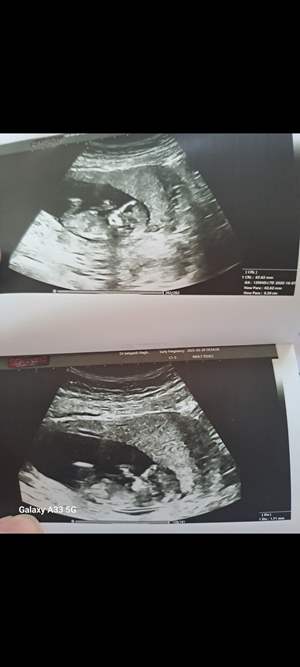

سؤال احتمال 70 درصد سونوی NT گفت دختره... درسته؟